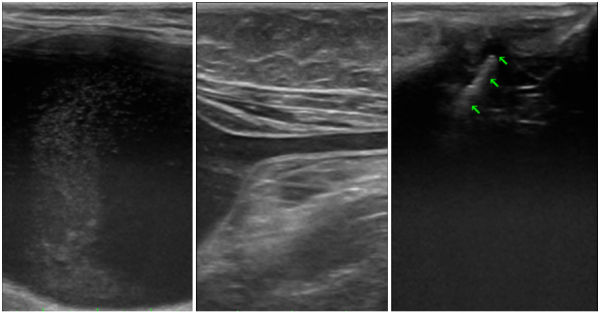

정확한 진단을 위해 초음파 기반의 영상검사를 실시하였으며,

이를 통해 요관결석과 요관폐색 여부를 확인하였습니다.

검사에서 좌측 요관결석이 확인되었고,

시간이 지나며 요관이 완전히 막히면서

심한 수신증으로 급격히 악화되었습니다.

초음파 검사에서 방광의 심한 팽만과 함께 요도가 전반적으로 확장되어 있고,

요도 원위부 내 다량의 사결석과 결석이 관찰되었습니다.